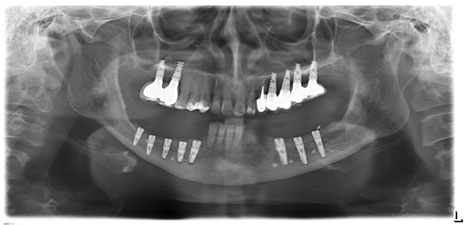

По согласованию с пациенткой проведено удаление 33, 34, 38, 43, 44 зубов, а также произведены трапециевидные разрезы слизистой оболочки альвеолярного отростка в области 35-47 и 45-47.

Отслоены слизисто-надкостничные лоскуты.

С помощью Пьезотома проведена операция латерализации и постеориоризации нижнечелюстного нерва в области 35-37 и 45-47.

С помощью боров и костных конденсоров XiVE сформированы 7 лож имплантатов. Введены имплантаты XiVE в области 35, 36, 37 – D3,4/L13; 45, 46, 47 – D3,4/L9,5; 44 – D3,8/L9,5; 43 – D3,8/L11.

Костной крошкой заполнены дефекты в пришеечных областях имплантатов, уложен BIO OSS.

Сверху, перекрывая гребень, установлены барьерные мембраны Bio-Gide и фиксированы 6-ю мембранными гвоздями.

Мобилизован лоскут. Наложены швы профимед. Аппликация Solcoseril Dental